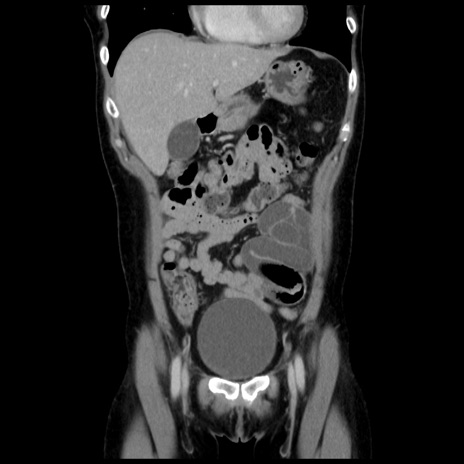

症例10(冠状断像)

【症例】 50歳代女性

【主訴】 腹痛

【現病歴】前日生レバーを食べた。今朝に排便あり。 昼前に突然発症の腹痛を生じ、当院救急外来を受診した。

【既往歴】 子宮筋腫にてで子宮全摘後

【身体所見】 意識清明、腹部:平坦、軟、下腹部やや左を中心に圧痛・反跳痛あり、筋性防御あり

【データ】WBC 7800、CRP 0.07